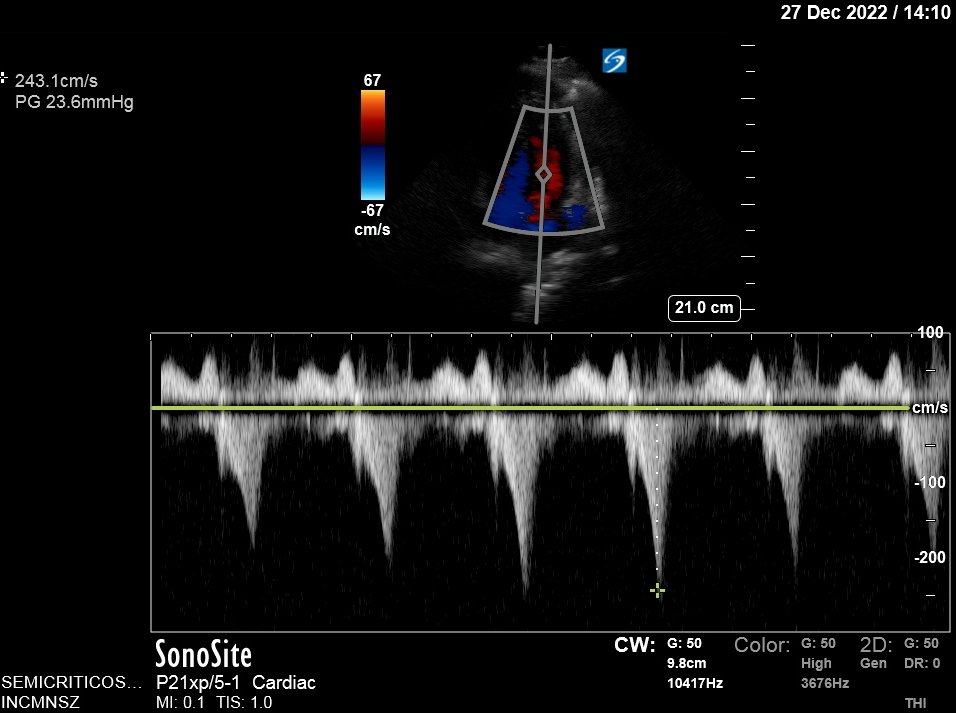

Also..LV looks very empty. LV walls can get too close together and obstruct the flow of blood!

Obstruction causes blood to speed up! (think of thumb on a hose).

Velocity is 3.5 m/s (very fast) with a gradient of 50 mmHg! This is Hemodynamically significant obstruction!

Fluid did help: BP now 105/69, gradient improved from 50 to 24 mmHg!